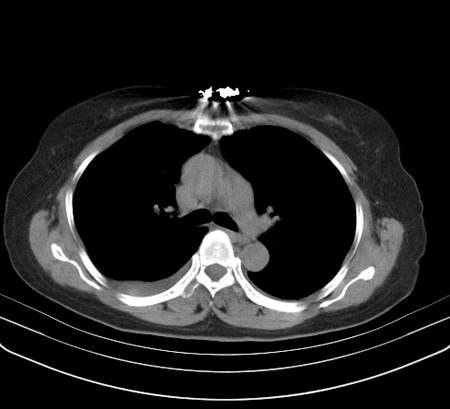

以下是引用余辉在2009-2-19 20:10:00的发言:[br]多考虑急性感染性病变,右中叶尚可见多枚小斑片状影,多为化脓性肺炎,双侧胸腔积液

以下是引用随光逐影在2009-2-19 20:33:00的发言:[br]1)考虑右肺炎症;建议抗炎治疗后复查。2)双侧胸腔积液(以右侧为甚)。

以下是引用花凤凰在2009-2-19 20:46:00的发言:[br]病人有发热,胸痛急性起病,主要病变位于右肺中叶外侧段,呈楔行改变,位于外带胸膜下,考虑为肺梗塞可能!!!!!!!!!!!!!!!!!!!!!!!!!!!!!!!!!!!